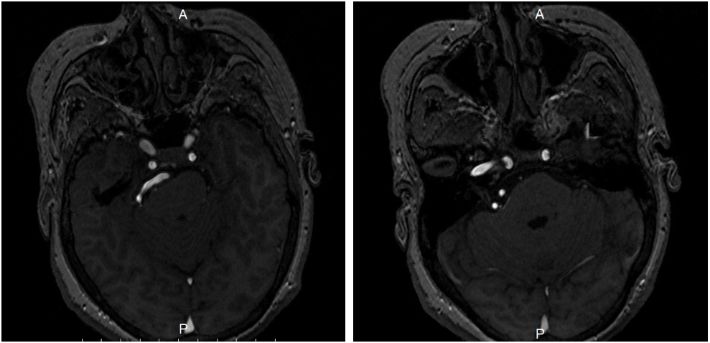

术中证实我们对影像结果的判断,迂曲的椎动脉同时压迫面神经及三叉神经,面神经受压变形,三叉神经被压向天幕呈薄片状,尝试多点推开椎动脉,但对面神经仍有向后压迫,无法实施“多点架桥”,故选择“生物胶悬吊”。

![]()

迂曲的椎动脉压迫面神经,面神经受压变形。

迂曲的椎动脉压迫三叉神经,推开椎动脉可见三叉神经被压向天幕呈薄片状。